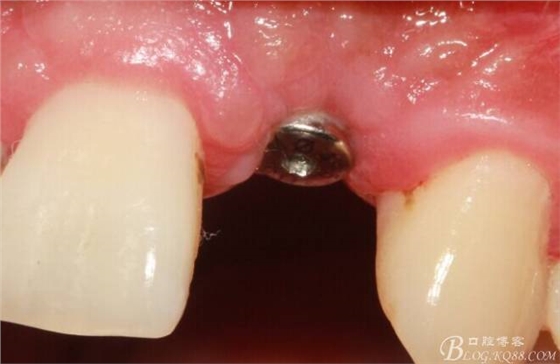

術(shù)后1個(gè)月。

術(shù)后5個(gè)月。